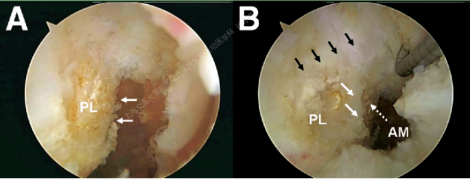

ACL的双束结构

根据ACL在胫骨止点相对位置,分为前内侧束(Antero-medial bundle,AM束)、后外侧束(Postero-lateral bundle,PL束)。膝关节伸屈时,AM、PL束发挥不同功能(伸膝时PL束紧张,屈膝时AM束紧张)

PL束:屈膝90°时,股骨后髁软骨缘前5-8mm;AM束:股骨后缘远侧5-6mm。